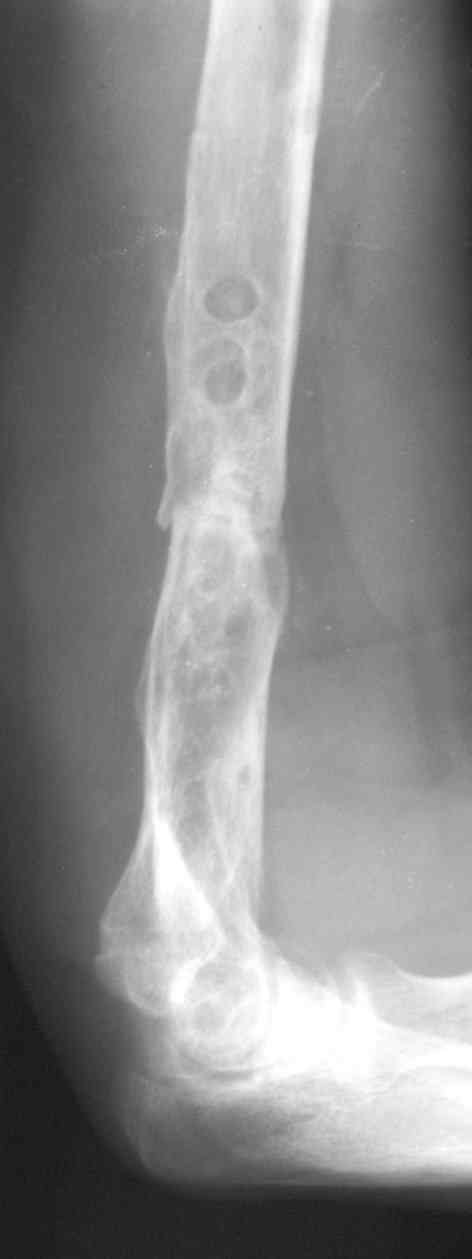

В подобном случае мы бы применили чрескостный остеосинтез. Пример - в приложении.